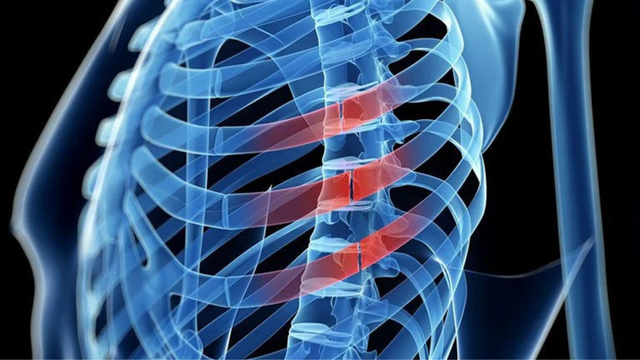

Gãy xương